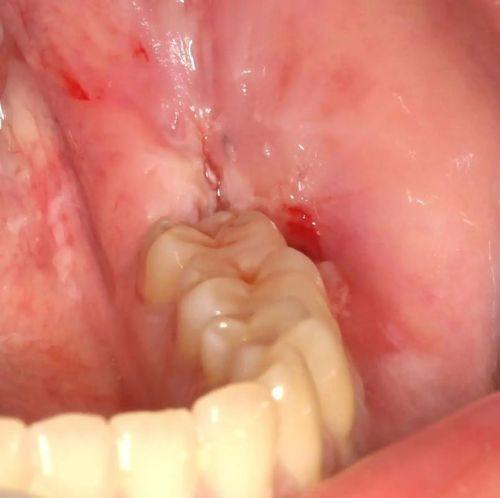

拔牙:擅长微创智齿拔除,创伤小,术后修复快,降低患者拔牙过程中的不适感。